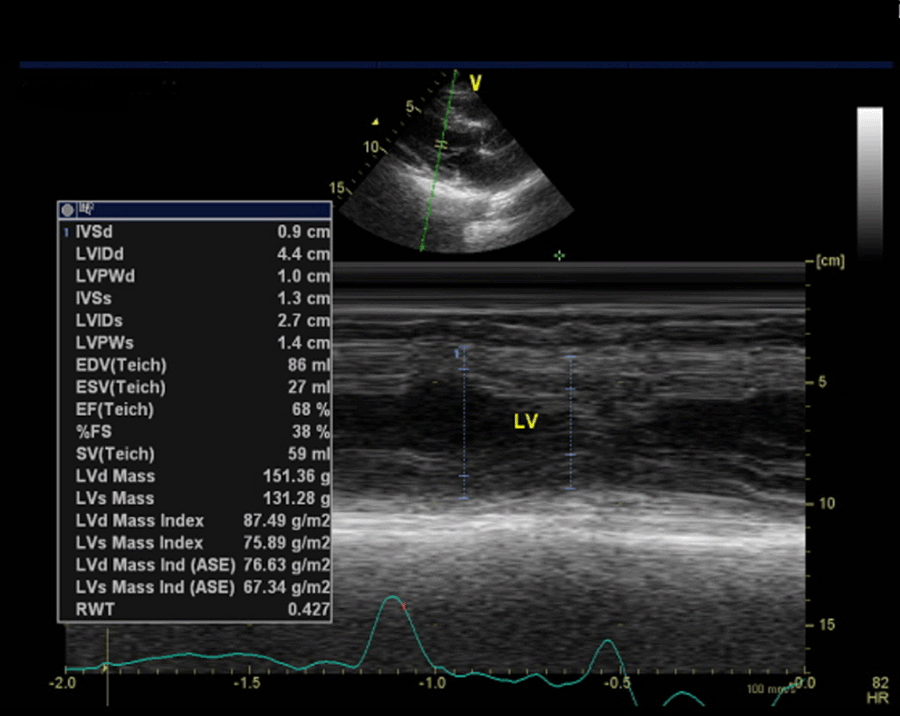

After three weeks of leaving the hospital, the patient was asked to undergo echocardiography. The results of this examination demonstrated that there was mild mitral regurgitation with normal cardiac chamber dimensions. The left ventricular systolic function seemed normal with ejection fraction by Teich being 68%, as did the left ventricular diastolic function with E/A being 0.87 (Figure 7). On the other hand, the right ventricular systolic function appeared normal with tricuspid annular plane systolic excursion accounting for 1.8 cm.